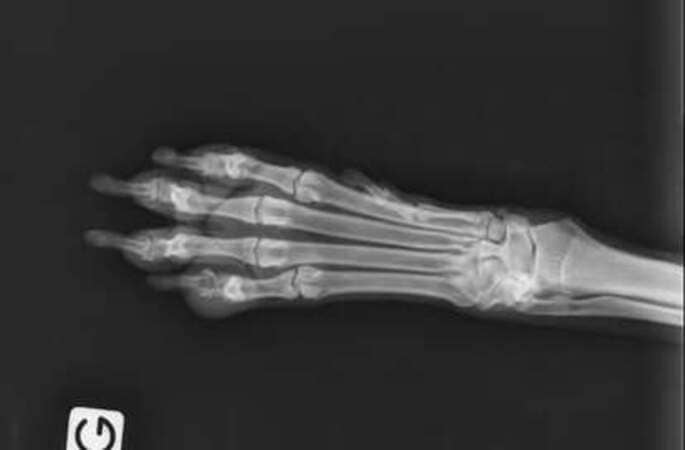

Le bout de la patte de Pachou est bizarroïde, on tente un traitement antibio voir si ça fonctionne. Si ça ne fonctionne pas, ce sera certainement retrait du doigt si c’est plus sérieux, si c’est un carcinome épidermoïde (mais d’après la radio, non). Pas de pus, mais gonflé, mais pas de lyse non plus. J’ai acheté aussi de l’hexamidine transcutanée pour lui faire trempette de son bout de doigt. Donc antibio 21 jours et on voit. Je vais lui rajouter une infusion de thym en prime.